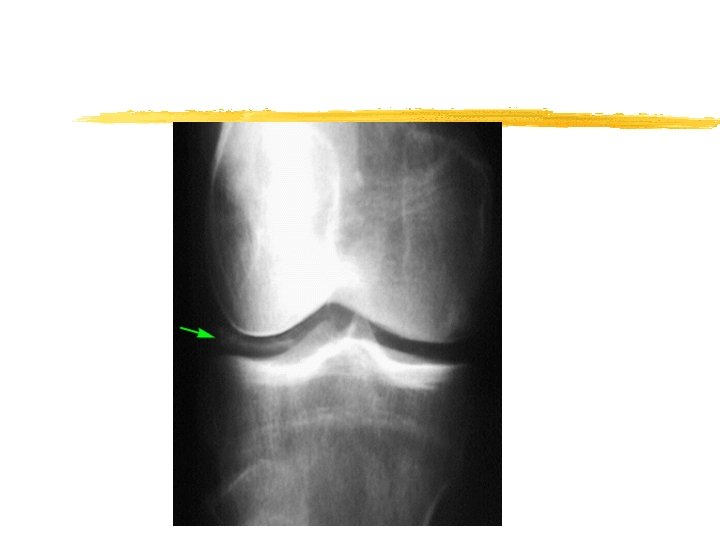

Imaging z Chondrocalcinosis

Pseudo-osteoarthritis z Pattern of joint involvement z Knee, MCP, wrist, elbow , shoulder z More likely to be symmetrical z Chondrocalcinosis